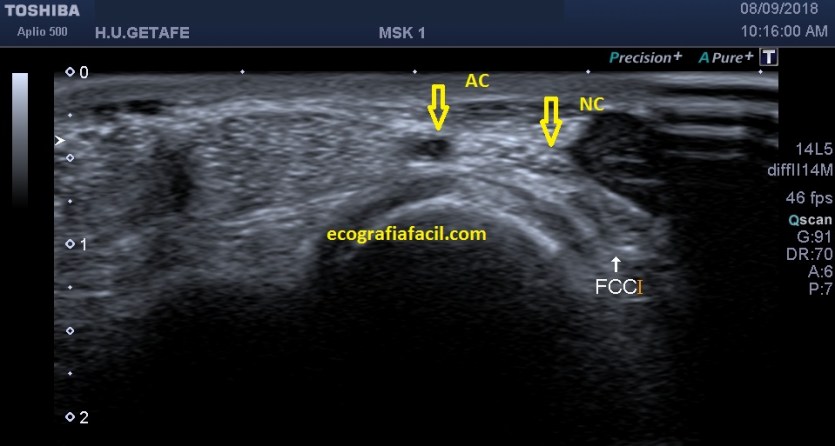

Ahora el corte transversal…